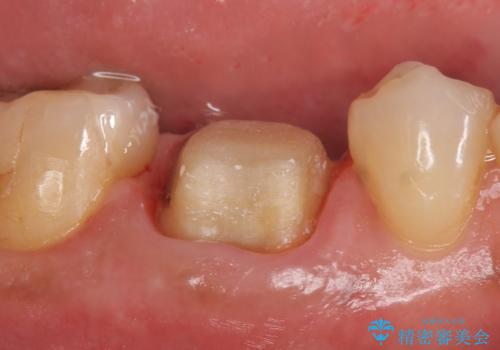

- ものを咬むと右下の奥歯が疼くといらっしゃった方の症例です。

検査の結果X線上で右下6に根尖病変を認めたため、再根管治療を行いました。

症状が治まったのを確認後、オールセラミッククラウンによる補綴を行いました。